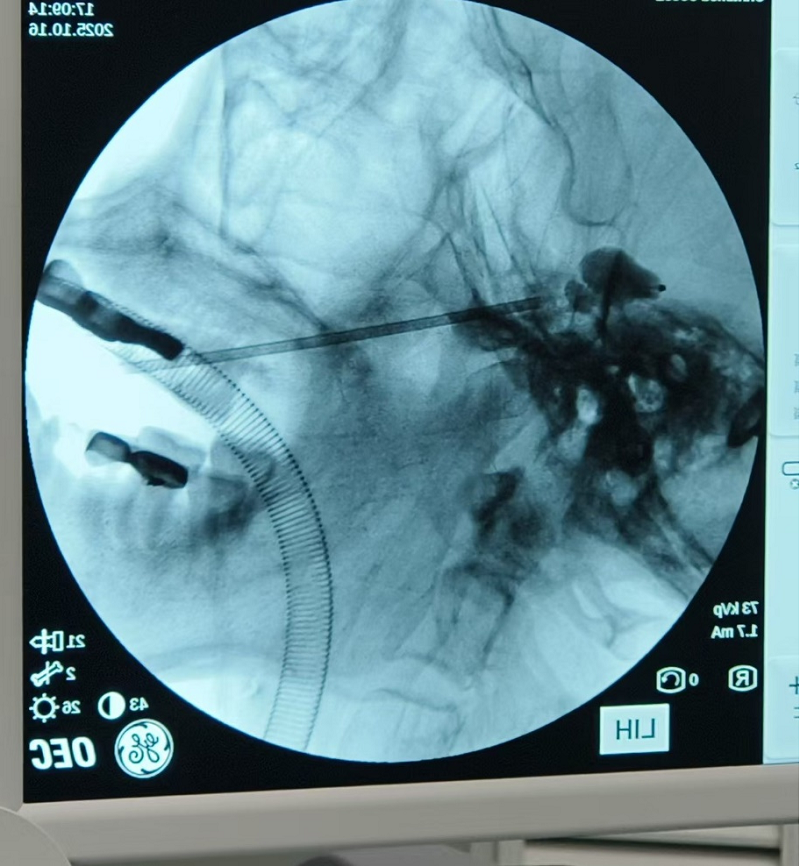

10月18日,永州市江华瑶族自治县民族中医医院疼痛科团队在中南大学湘雅三医院疼痛科专家周浩宬的帮扶指导下,开展了院内首例三叉神经半月节球囊压迫术,为一位多年饱受“三叉神经痛”困扰的患者解除了病痛。

该患者反复左侧颜面部疼痛多年,曾于其他医院行三叉神经射频热凝术,术后半年复发,术前口服卡马西平等药物治疗不佳,严重影响患者的生活质量。周浩宬与中医院团队讨论后,认为患者目前三叉神经痛诊断明确,患者要求行微创手术意愿强烈,可以考虑行三叉神经半月节球囊压迫术。

手术过程中,周浩宬“手把手”地对江华瑶族自治县民族中医医院的疼痛科医生进行了现场教学指导,深入浅出地讲解了手术要点、操作技巧及围术期管理,将先进的疼痛诊疗理念和技术毫无保留地传授给基层同仁。术后病人恢复良好,疼痛完全解除。

周浩宬介绍,该微创手术仅需在面部穿刺一个针眼,通过导入微球囊精准压迫痛觉神经纤维,便能迅速、有效地阻断疼痛,具有创伤小、恢复快、疗效确切等优势。